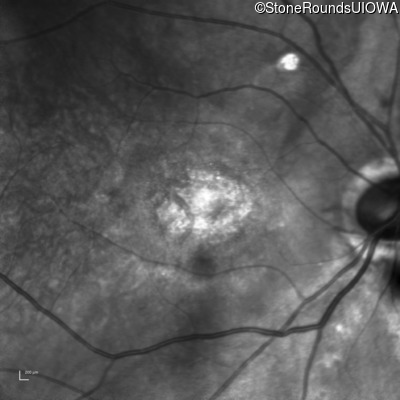

XL Cone and Cone Rod Dystrophy (IA1bi)

XL Cone and Cone Rod Dystrophy (IA1bi)

This 52 year old man had normal vision until his mid 30's when he began to have trouble distinguishing colors. the issuing 10 years he had a gradual loss of visual acuity accompanied by increasing photophobia.

| XL Cone and Cone Rod Dystrophy | RPGR | Gly1093 del2gGA | XL |